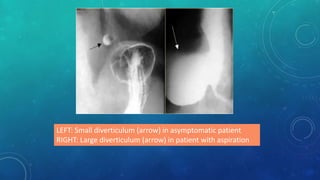

LEFT: Small diverticulum (arrow) in asymptomatic patient

RIGHT: Large diverticulum (arrow) in patient with aspiration